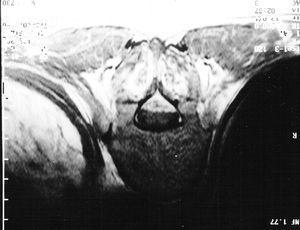

Paciente varón de 76 años de edad que ingresó en la unidad de cuidados críticos por politraumatismo secundario a accidente de tráfico. Presentaba fractura de arcos costales izquierdos con hemoneumotórax y contusión pulmonar, laceración esplénica, hemoperitoneo y fractura diafisaria de fémur izquierdo. Fue intervenido quirúrgicamente para estabilización y tratamiento de las lesiones. A los 7 días de ingreso se colocó un catéter epidural para control del dolor y facilitar el proceso de desconexión de la ventilación mecánica. El hemograma previo a la colocación del catéter no demostró alteraciones de la coagulación. Tras la colocación del catéter epidural se inició una perfusión continua con bupivacaína al 0,25% y fentanilo 0,6 µg/ml a 7 ml/h. A los 8 días el paciente presentó paraplejia bilateral que fue interpretada como posible bloqueo motor residual por bupivacaína; se decidió retirar el catéter y mantener una actitud expectante. El intervalo de tiempo entre la dosis de HBPM (enoxaparina 40 mg/24 h subcutánea) y la colocación del catéter epidural fue de 15 horas; entre la administración de HBPM y la retirada del catéter fue de 23 horas. Asimismo, el tiempo transcurrido entre la retirada del catéter y la administración posterior de HBPM fue de 1 hora. El paciente fue recuperando progresivamente la sintomatología neurológica pero mantuvo plejia (fuerza 0/5) en la pierna derecha. Se realizó una resonancia magnética en la que se objetivó un hematoma epidural entre los espacios D9-L1 (fig. 1). Seguidamente se realizó una laminectomía descompresiva y extracción del hematoma. El retraso en el diagnóstico desde el inicio de los síntomas fue superior a 72 horas. Un mes más tarde el paciente no había recuperado la movilidad del miembro inferior derecho.

Figura 1. Corte coronal torácico a nivel D11 en la resonancia magnética en el que se observa hematoma epidural.